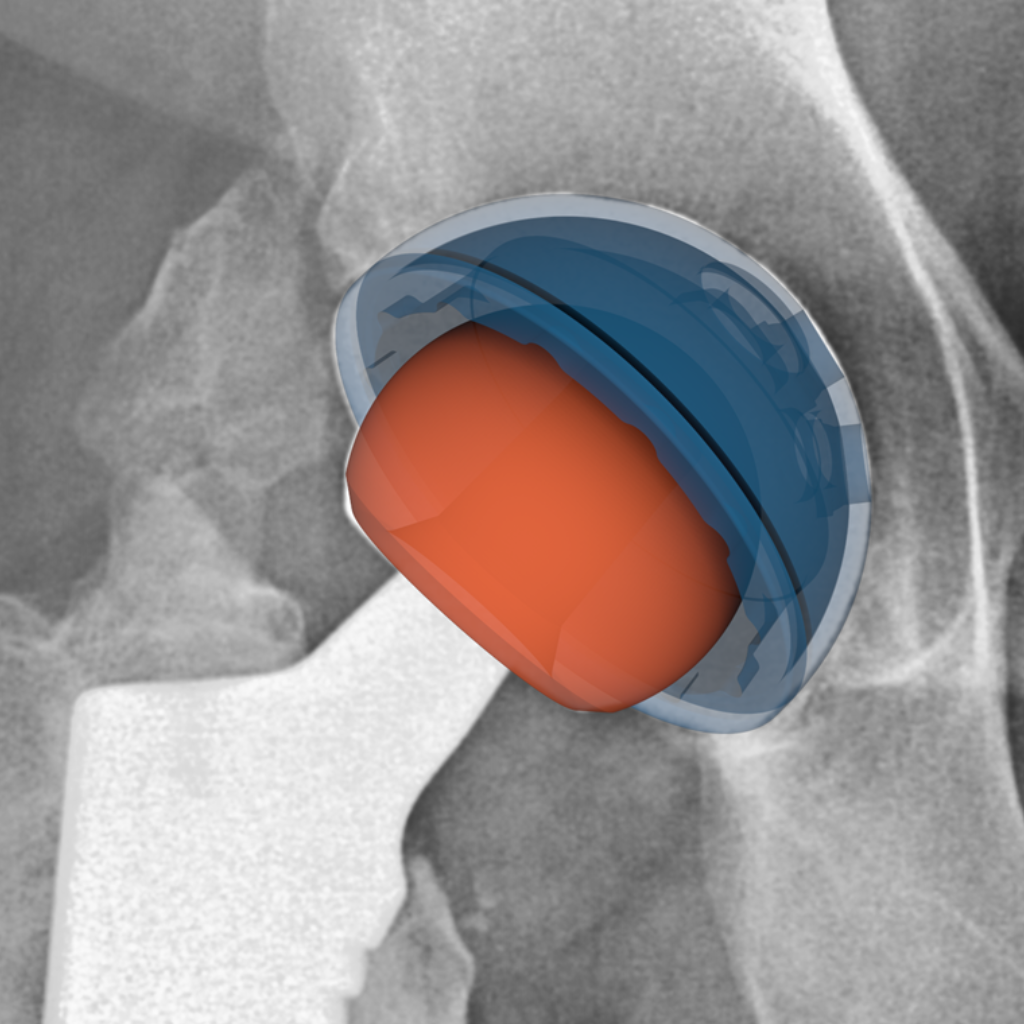

Implantat-Positionierung und -Leistungsanalyse in der Hüftendoprothetik.

Wir verfügen über umfassende Erfahrung in der Unterstützung von Herststellern von Hüft-Totalendoprothesen (TEP) mit radiographischer Analyse während der gesamten Produktentwicklung – von primären TEP-Eingriffen über Revisionsprozeduren bis hin zur Post-Market-Überwachung.

Unser Team hat proprietäre 2D-3D-Bildregistrierungstechniken entwickelt und validiert, die präzise Implantatpositionierungsmetriken (Pfanneninklination und -anteversion) sowie lineare Verschleißmessungen aus klinischen Standardröntgenaufnahmen extrahieren. Diese Methodik wurde in mehreren klinischen Studien zur Unterstützung regulatorischer Einreichungen angewendet und ermöglicht Bewertungen der Gerätesicherheit und -wirksamkeit ohne spezialisierte Bildgebungsprotokolle.

Unsere TEP-Expertise umfasst:

- Primäre und Revisionsverfahren

- Komponentenpositionierungsanalyse für konventionelle und robotergestützte Eingriffe

- Langzeit-Migrationsbeurteilung (Femurschaft-Subsidence, Pfannenmigration)

- Polyethylen-Liner-Verschleißquantifizierung

- Osseointegrationsbewertung von Pfannenkomponenten

- Überwachung der Geräteintegrität und Aufhellungssaum-Detektion

Wir haben Hersteller von Hüft-TEP-Implantaten dabei unterstützt, robuste, regulatorisch konforme Evidenz über verschiedene Implantatdesigns und chirurgische Ansätze hinweg zu generieren.

Hüfte

Inklination und Anteversion der Hüftpfanne

Unter Pfanneninklination versteht man den Winkel in Grad (°) der Pfannenoberfläche gegenüber der horizontalen (medio-lateralen) Achse.

Die Anteversion der Pfanne ist der Winkel in Grad (°) der Pfannenoberfläche gegenüber der Symmetrieachse der Pfanne in der Frontalebene.

Zur Beurteilung dieser Parameter sind CAD-Modelle der Implantate erforderlich.

Typ

Quantitativ

Bildtyp

AP Beckenaufnahme

Maßeinheit

Grad (°)